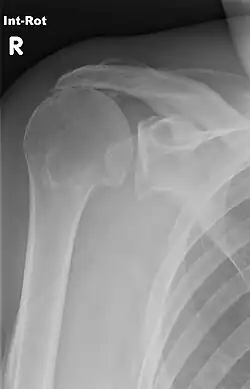

Im Zuge von degenerativen Veränderungen der Supraspinatussehne kommt es regelhaft zu entzündlichen Veränderungen der Bursa subacromialis im Sinne einer (aseptischen) Bursitis subacromialis. Dabei verklebt die Gleitschicht und kommt ihrer Funktion nicht mehr nach. In der Folge verschmälert sich diese Gleitschicht, gleichzeitig wird der M. supraspinatus dünner. Es resultiert ein „Schulterhochstand“, also eine Verschmälerung des Subacromialraums. Im weiteren Verlauf reißt der M. supraspinatus (Rotatorenmanschettenruptur) und kann dann seiner Funktion der Abduktion im Schultergelenk nicht mehr nachkommen. Für den Betroffenen äußert sich dieser Zustand im Sinne von chronischen Schmerzen bis hin zum Bild der „Frozen Shoulder“, also einer schmerzhaften Bewegungsunfähigkeit des gesamten Schultergelenks.[2]